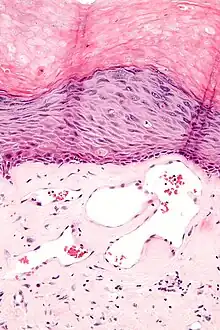

Histology

Angiokeratomas characteristically have large dilated blood vessels in the superficial dermis and hyperkeratosis (overlying the dilated vessels).